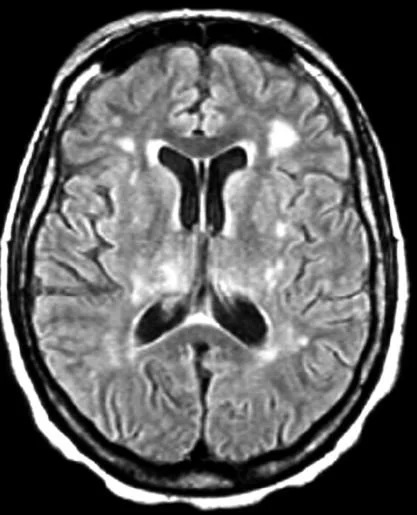

What do you notice on his MRI?

T2-weighted FLAIR shows T2 signal increase in the white matter, basal ganglia and L insula consistent with his meningoencephalitis. His LP was positive for lymphocytes and tested positive for West Nile IgM.